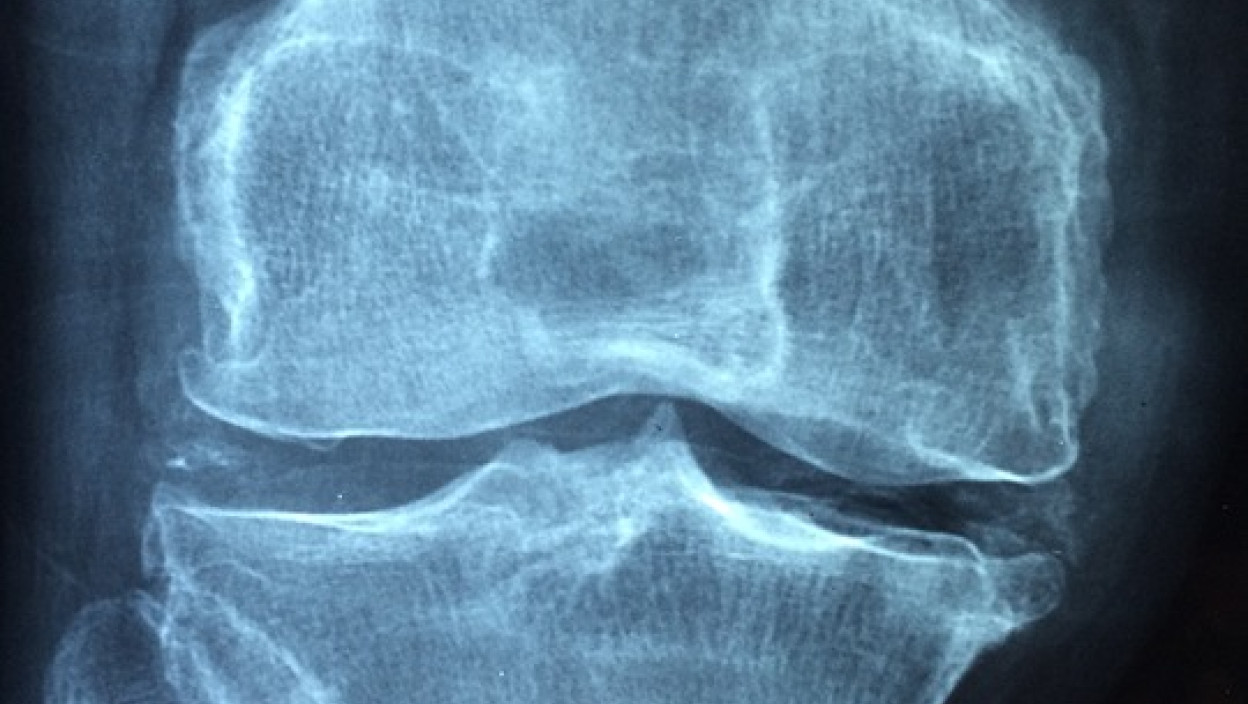

У Србији артритис мучи 60.000 људи

БЕОГРАД: У Србији од хроничних артритиса (ХАР) болује око 60.000 људи, од чега је 35.000 оболелих од реуматоидног артритиса (РА), а постављање дијагнозе у просеку траје око годину дана, речено је на округлом столу ''''Не одлажи, време је за рад'''' и указано да су ХАР аутоимуне системске болести које највише погађају млађу, радно активну популацију.

Реуматолог Предраг Остојић са Института за радиологију Србије нагласио је да је рано откривање хроничних артритиса од пресудног значаја за лечење болести које су, како је рекао, у прве две године најагресивније и најдеструктивније по зглобове.

''Важно је да се дијагноза постави у прва три месеца од појаве првих тегоба. Ако тада почне лечење пацијенти уз адекватну терапију могу потпуно нормално да живе, али ако се касни, оштећења могу бити трајна'', упозорио је Остојић.